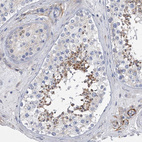

Immunohistochemical staining of human duodenum shows strong cytoplasmic positivity in lymphoid cells.